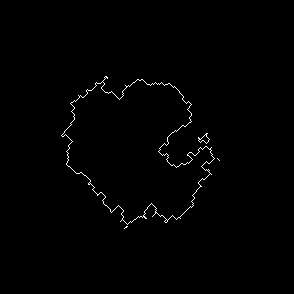

For segmentation in this particular case we applied thresholds values 0.01 and 0.02, made after normalization and it has weak effect on final results Fig.5. Perimeter shape is different but still it is close to desired boundaries, detected by an eye.

Refer to caption

(a) Threshold=0.01, Frame 1

(b) Result of segmentation, Frame 1

(c) Threshold=0.02, Frame 1

(d) Result of segmentation, Frame 1

(e) Manual drawing of cell contour, Frame 1

(f) Threshold=0.01, Frame 2

(g) Result of segmentation, Frame 2

(h) Threshold=0.02, Frame 2

(i) Result of segmentation, Frame 2

(j) Manual drawing of cell contour, Frame 2

Figure 5: Segmentation process and manual segmentation, of Frame 1 and 2 of sample sequence. Contours image(d) obtained after segmentation with different threshold values is close to manual segmentation(e) and can be considered as true detection